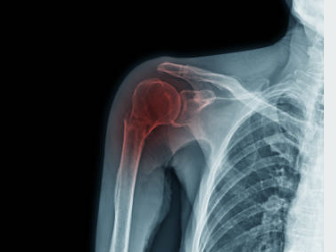

어깨 회전근개는 상완뼈와 견갑골 사이에 위치한 네 개의 근육과 그 근육들을 연결하는 건으로 이루어진 구조입니다. 이는 상체를 움직이는 데 있어서 중요한 역할을 합니다. 어깨 회전근개는 팔을 들거나, 회전하거나, 상체를 앞으로 내밀 때 근육을 동원하여 이를 가능하게 합니다. 어깨 회전근개는 근육과 건으로 이루어져 있기 때문에 손상이 발생하면 회복이 어렵습니다.

회전근개 파열은 어깨 부상 중 가장 일반적인 손상 중 하나이며, 일상생활에서 많이 발생합니다. 회전근개 파열의 증상은 다음과 같습니다.